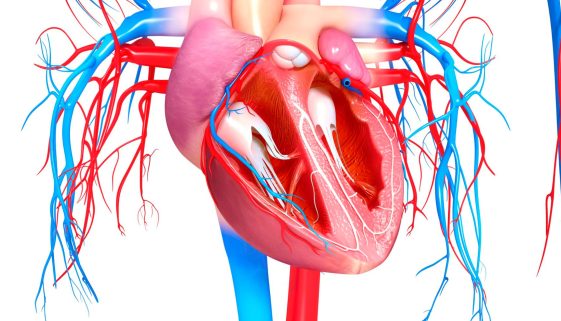

دليل شامل لتوسيع صمامات القلب

تُعد صحة القلب من المواضيع الحيوية التي تؤثر بشكل مباشر على جودة الحياة. يعد توسيع صمامات القلب أحد الإجراءات الطبية المهمة التي تهدف إلى تحسين أداء القلب لدى المرضى الذين يعانون من مشاكل في الصمامات القلبية. في هذه المقالة، سنستعرض نصائح وتعليمات تثقيفية حول تحسين صحة القلب وتوسيع صماماته، مع […]